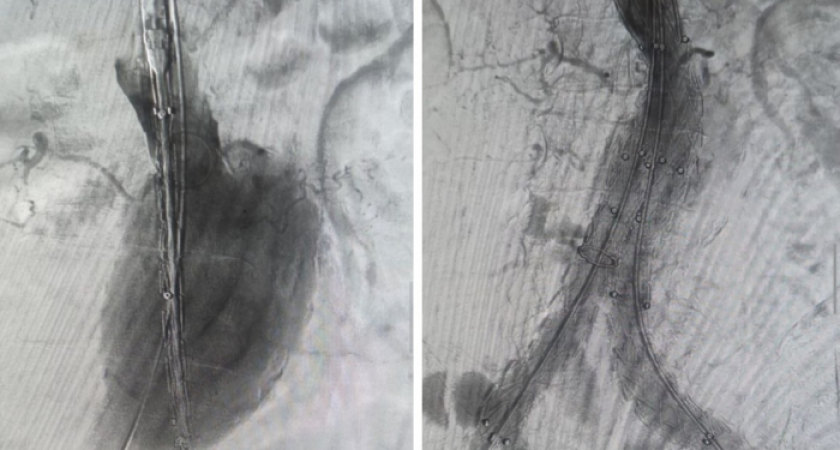

Вместо рискованного открытого вмешательства медики применили малотравматичный метод установки стент-графта, сообщили в облздраве.

Специальная конструкция — стент-графт — была доставлена по сосудам и установлена внутрь аорты. Стент, представляющий собой прочный металлический каркас, создал новый канал для кровотока, а тканевая часть укрепила стенку сосуда, предотвратив ее разрыв. Это позволило избежать жизнеугрожающих осложнений.